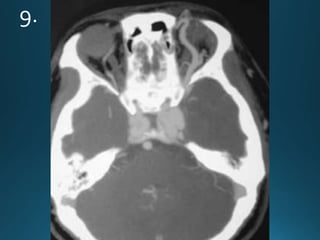

Sturge-Weber syndrome (SWS), or encephalotrigeminal angiomatosis, is a phakomatosis

characterised by facial port wine stains and pial angiomas

CT

detects subcortical calcification at an earlier age than plain film and can also demonstrate

associated parenchymal volume loss

'tram-track' subcortical calcification

MRI

T1: signal of affected region largely normal, with anatomic volume loss evident at older age

T1 C+ (Gd)

prominent leptomeningeal enhancement in affected area

T2

low signal in white matter subjacent to angioma representing

calcification later in life

abnormal deep venous drainage seen as flow voids

GE/SWI/EPI: sensitive to calcification, seen as regions of signal drop out

Sturge-Weber syndrome (SWS),or encephalotrigeminal angiomatosis, is a phakomatosis characterised by facial port wine stains and pial angiomas CT detects subcortical calcification at an earlier age than plain film and can also demonstrate associated parenchymal volume loss 'tram-track' subcortical calcification MRI T1: signal of affected region largely normal, with anatomic volume loss evident at older age T1 C+ (Gd) prominent leptomeningeal enhancement in affected area T2 low signal in white matter subjacent to angioma representing calcification later in life abnormal deep venous drainage seen as flow voids GE/SWI/EPI: sensitive to calcification, seen as regions of signal drop out